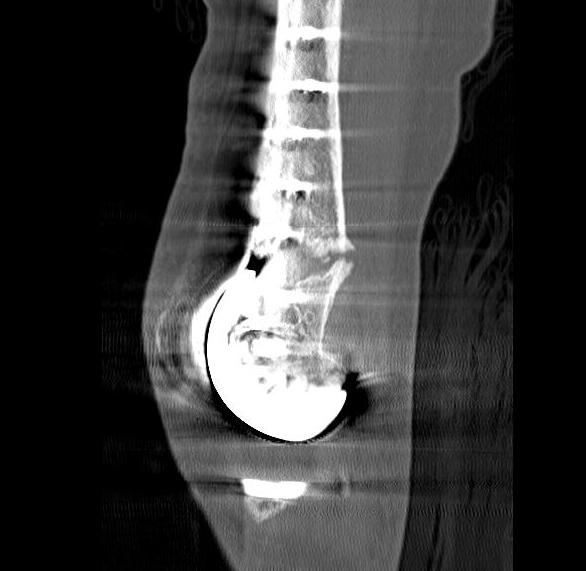

3.  Anterograde nail

Indications

- sufficient bone above implant for distal locking

Issues

- stress riser between femoral implant and nail

- must ensure correct alignment

TKR Femoral FractureTKR Femoral Nail APTKR Femoral Nail Lateral